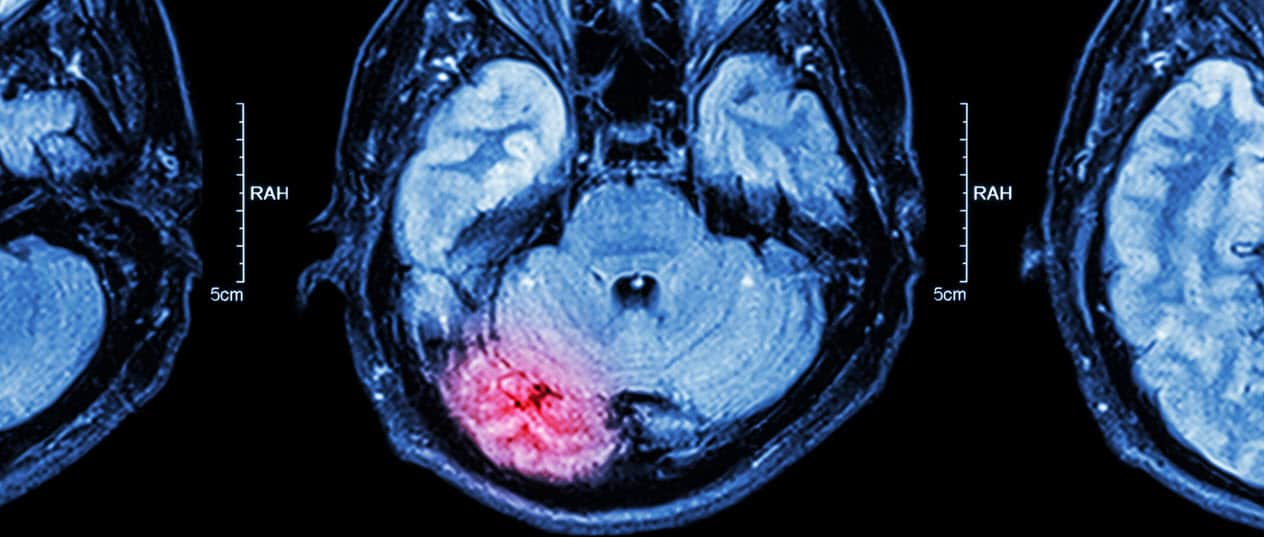

A medical professional will need to conduct several tests to diagnose a traumatic brain injury. Often victims will need to undergo an MRI or CT scan to determine if there is a TBI present. However, these scans do not always paint a full picture which is where a physical examination is also needed.